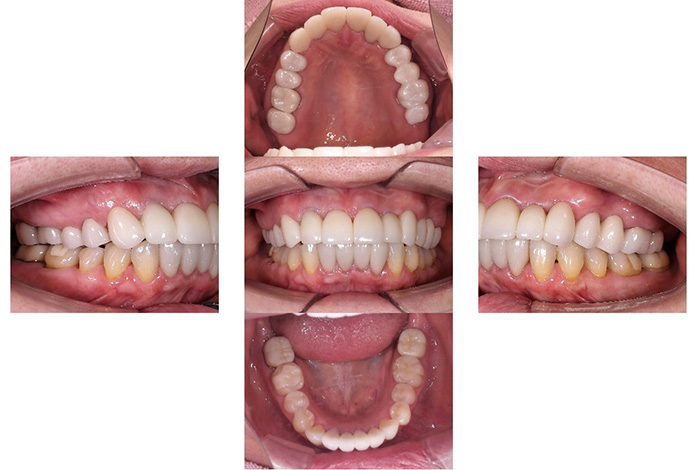

インビザラインによる全体矯正後に補綴治療を行い、咬合と審美性を総合的に改善した症例です。

まずマウスピース型矯正装置(インビザライン)により歯列および咬合関係を整え、その後、必要部位にジルコニア補綴を行いました。

矯正のみ・補綴のみではなく、両治療を組み合わせることで機能性と審美性の両立を目指した包括的治療です。

奥歯の噛み合わせと前歯の歯並びを同時に改善した症例(インビザライン+ジルコニア)

患者様は、奥歯でしっかり噛めないことと、前歯の歯並びの乱れを気にされ来院されました。診査の結果、前歯部の叢生(歯並びの乱れ)と、臼歯部の離開咬合(奥歯がしっかり噛み合っていない状態)が認められました。また、臼歯部には古い金属修復物が装着されており、機能面だけでなく審美面においても改善が必要な状態でした。

【治療後】

前歯の歯並びが整い、見た目の改善が認められました。また、奥歯でしっかり噛める状態となり、咬合機能の回復が得られています。

本症例では、歯並びの改善だけでなく、噛み合わせの回復と審美性の向上を同時に行っています。当院は一般歯科と矯正治療の両方に対応しているため、矯正治療後に別の医療機関で補綴治療を行う必要がなく、一貫した治療計画のもとで治療を完結することが可能です。また、奥歯の噛み合わせを矯正治療のみで改善する場合、治療期間が長くなることがありますが、本症例では補綴治療(アンレー)を併用することで、比較的短期間で咬合の改善を行いました。さらに、古い金属修復物をジルコニアに置き換えることで、見た目の改善と機能性の両立を図っています。